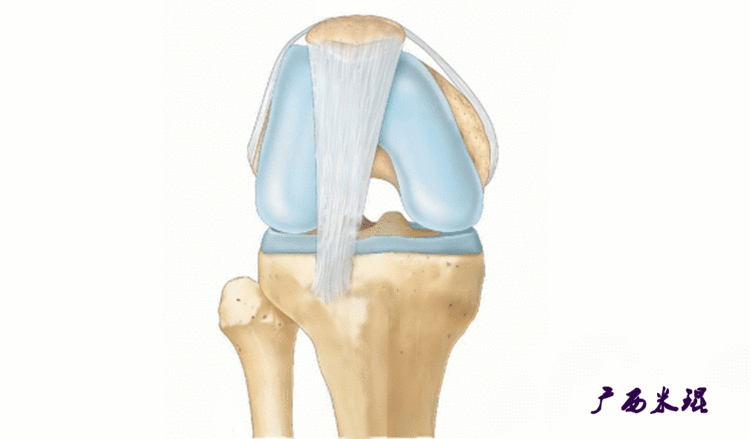

说到髌骨脱位,首先就要了解髌骨,髌骨是人体最大的籽骨,倒三角状位于膝关节前方,它的上缘与股四头肌腱相连,下缘通过髌韧带止于胫骨结节上,两侧为股四头肌扩张部,髌骨后方的凸面为光滑的关节面,与股骨下端内外髁之间的滑车凹面关节面形成关节。尽管股四头肌中的股直肌、股中间肌、股外侧肌的作用方向与髌韧带不在一条直线上,髌骨有向外突出的倾向,但因股内侧肌有向内上方牵拉作用力而使髌骨维持在正常位置。

髌骨脱位绝大部分是向外侧脱位,脱位后,髌股关节内侧的稳定结构,包括髌股关节内侧支持带、股内侧肌、内侧髌股韧带均被撕裂,导致膝关节腔内积肿,在髌骨脱位以及自行复位的过程中,髌骨内侧面与股骨髁外侧面撞击,会引起软骨损伤或骨软骨骨折,所以,千万不要把髌骨脱位当作成一个简单的疾病。